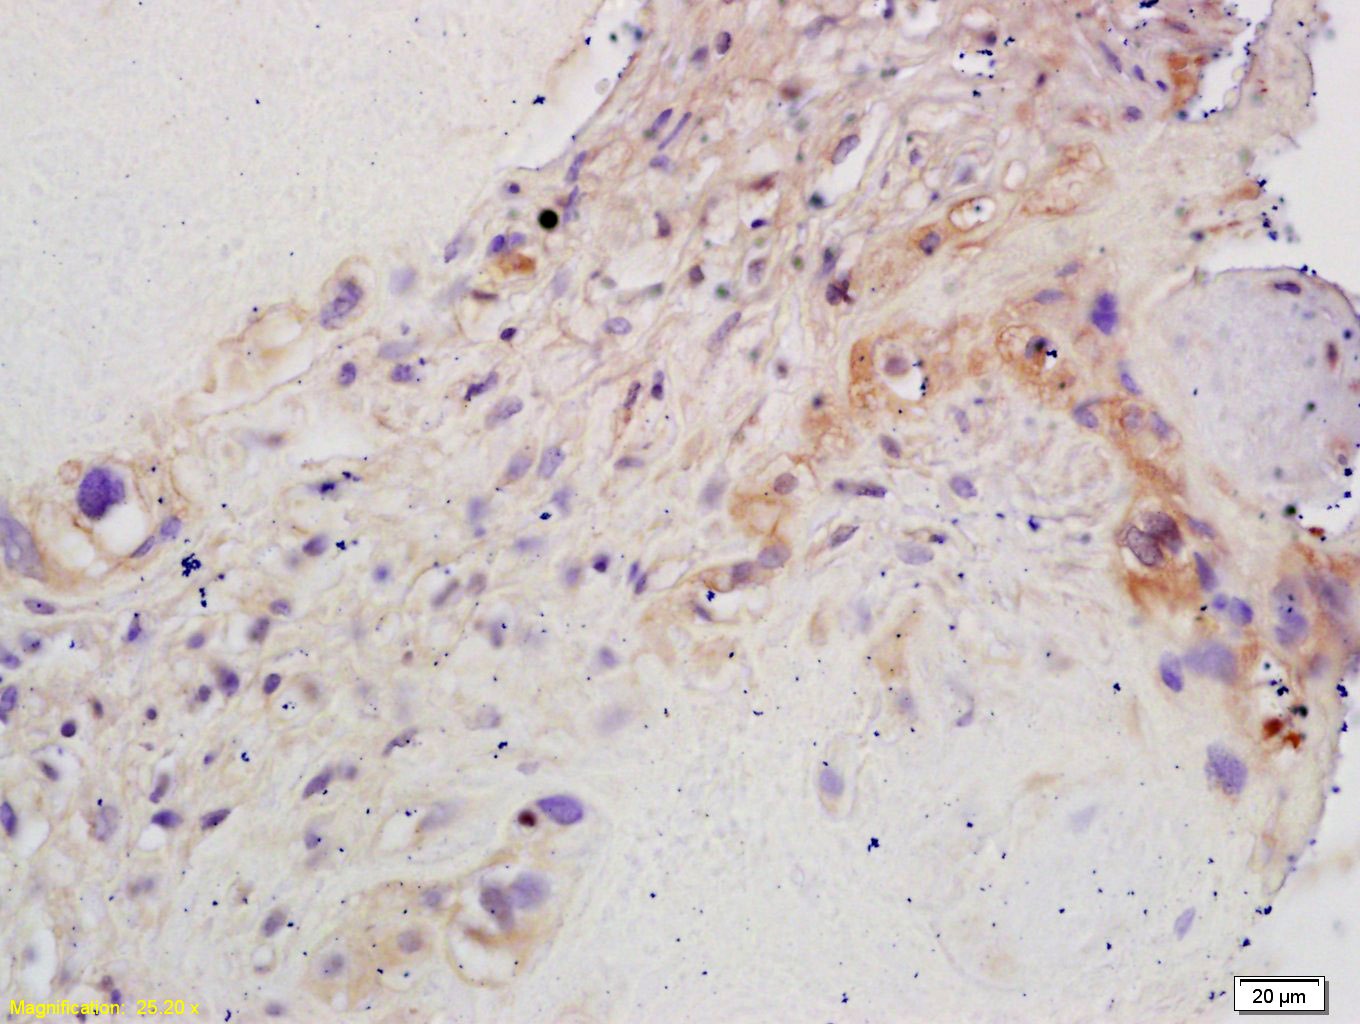

2. Tissue/cell: human placenta tissue; 4% Paraformaldehyde-fixed and paraffin-embedded;

Antigen retrieval: citrate buffer (0.01M, pH6.0), Boiling bathing for 15 min; Block endogenous peroxidase by 3% Hydrogen peroxide for 30 min; Blocking buffer (normal goat serum) at 37°C for 20 min;

Incubation: Anti-CYP19/CYP19A1 Polyclonal Antibody, Unconjugated (TMAB-00149) 1:200, overnight at 4°C, followed by conjugation to the secondary antibody and DAb staining.